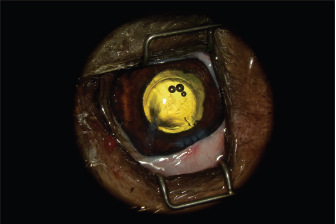

Fig. 2. Appearance of the eye after claw excision, corneal reconstruction, and pharmacological mydriasis. The tear of the anterior capsule is large and complex. The architecture of the lens is turned upside down.

The AC was stabilized by intracameral injection of a viscoelastic gel (hyaluronic acid 1.6%, Ophteis Bio) by a perforating keratotomy port at 12 o’clock. As the base of the claw was crenelated, it was not possible to remove it through the site of penetration, which is why another perforating keratotomy port was made at 10 o’clock. The claw was grasped with Bonn’s pliers and then gently removed. The entry point of the claw and the 10 o’clock port were sutured by single stitches using polyglactin 9/0 (Vicryl 9/0). The pupil was then dilated by injection of 1 ml of epinephrine at a concentration of 1 mg/ml into the AC. The anterior lens was ruptured, and a heterogeneous traumatic cataract had already developed (Fig. 2). The lens was, therefore, removed by phacoemulsification via the port at 12 o’clock. After removal of the masses by irrigation/aspiration, the tear of the anterior capsule was shaped before injection of an implant (PFI 4X, Medicontur). The keratotomy port at 12 o’clock was sutured by three single stitches with Vicryl 9/0 after the removal of residual viscoelastic material by suction irrigation. At this stage of the surgery, a tear of the endothelium and Descemet membrane was visible, following the most likely trajectory of the claw into the AC (Fig. 3). Water bubbles were already forming in the corneal stroma. An injection of 0.25 μg of tissue plasminogen activator (Actilyse®, BOEHRINGER INGELHEIM) was performed in the AC at the end of the intervention to limit postoperative fibrinous collection. The claw was sent to the laboratory for bacteriological analysis.